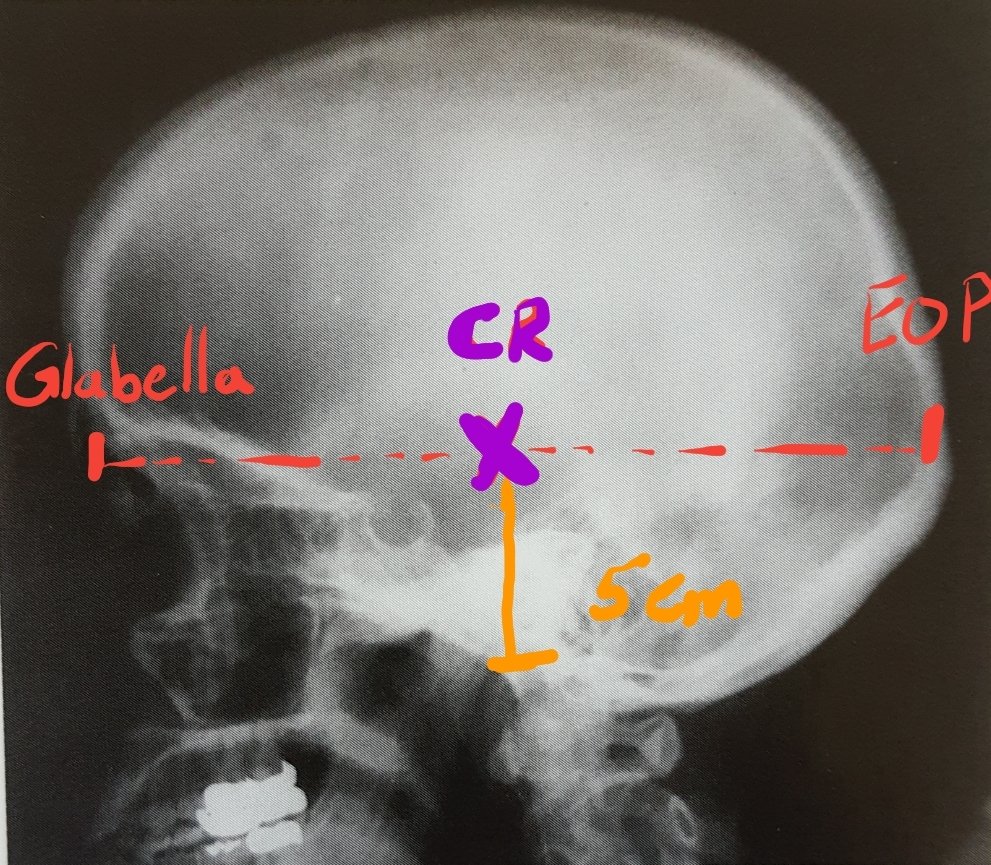

السنترCR/

-في منتصف المسافة بين

Inion(EOP) & glabella.

-أو بطريقة أخرى فوق EAM ب ٥سم.

الزاوية/

عمودية على الكاسيت.